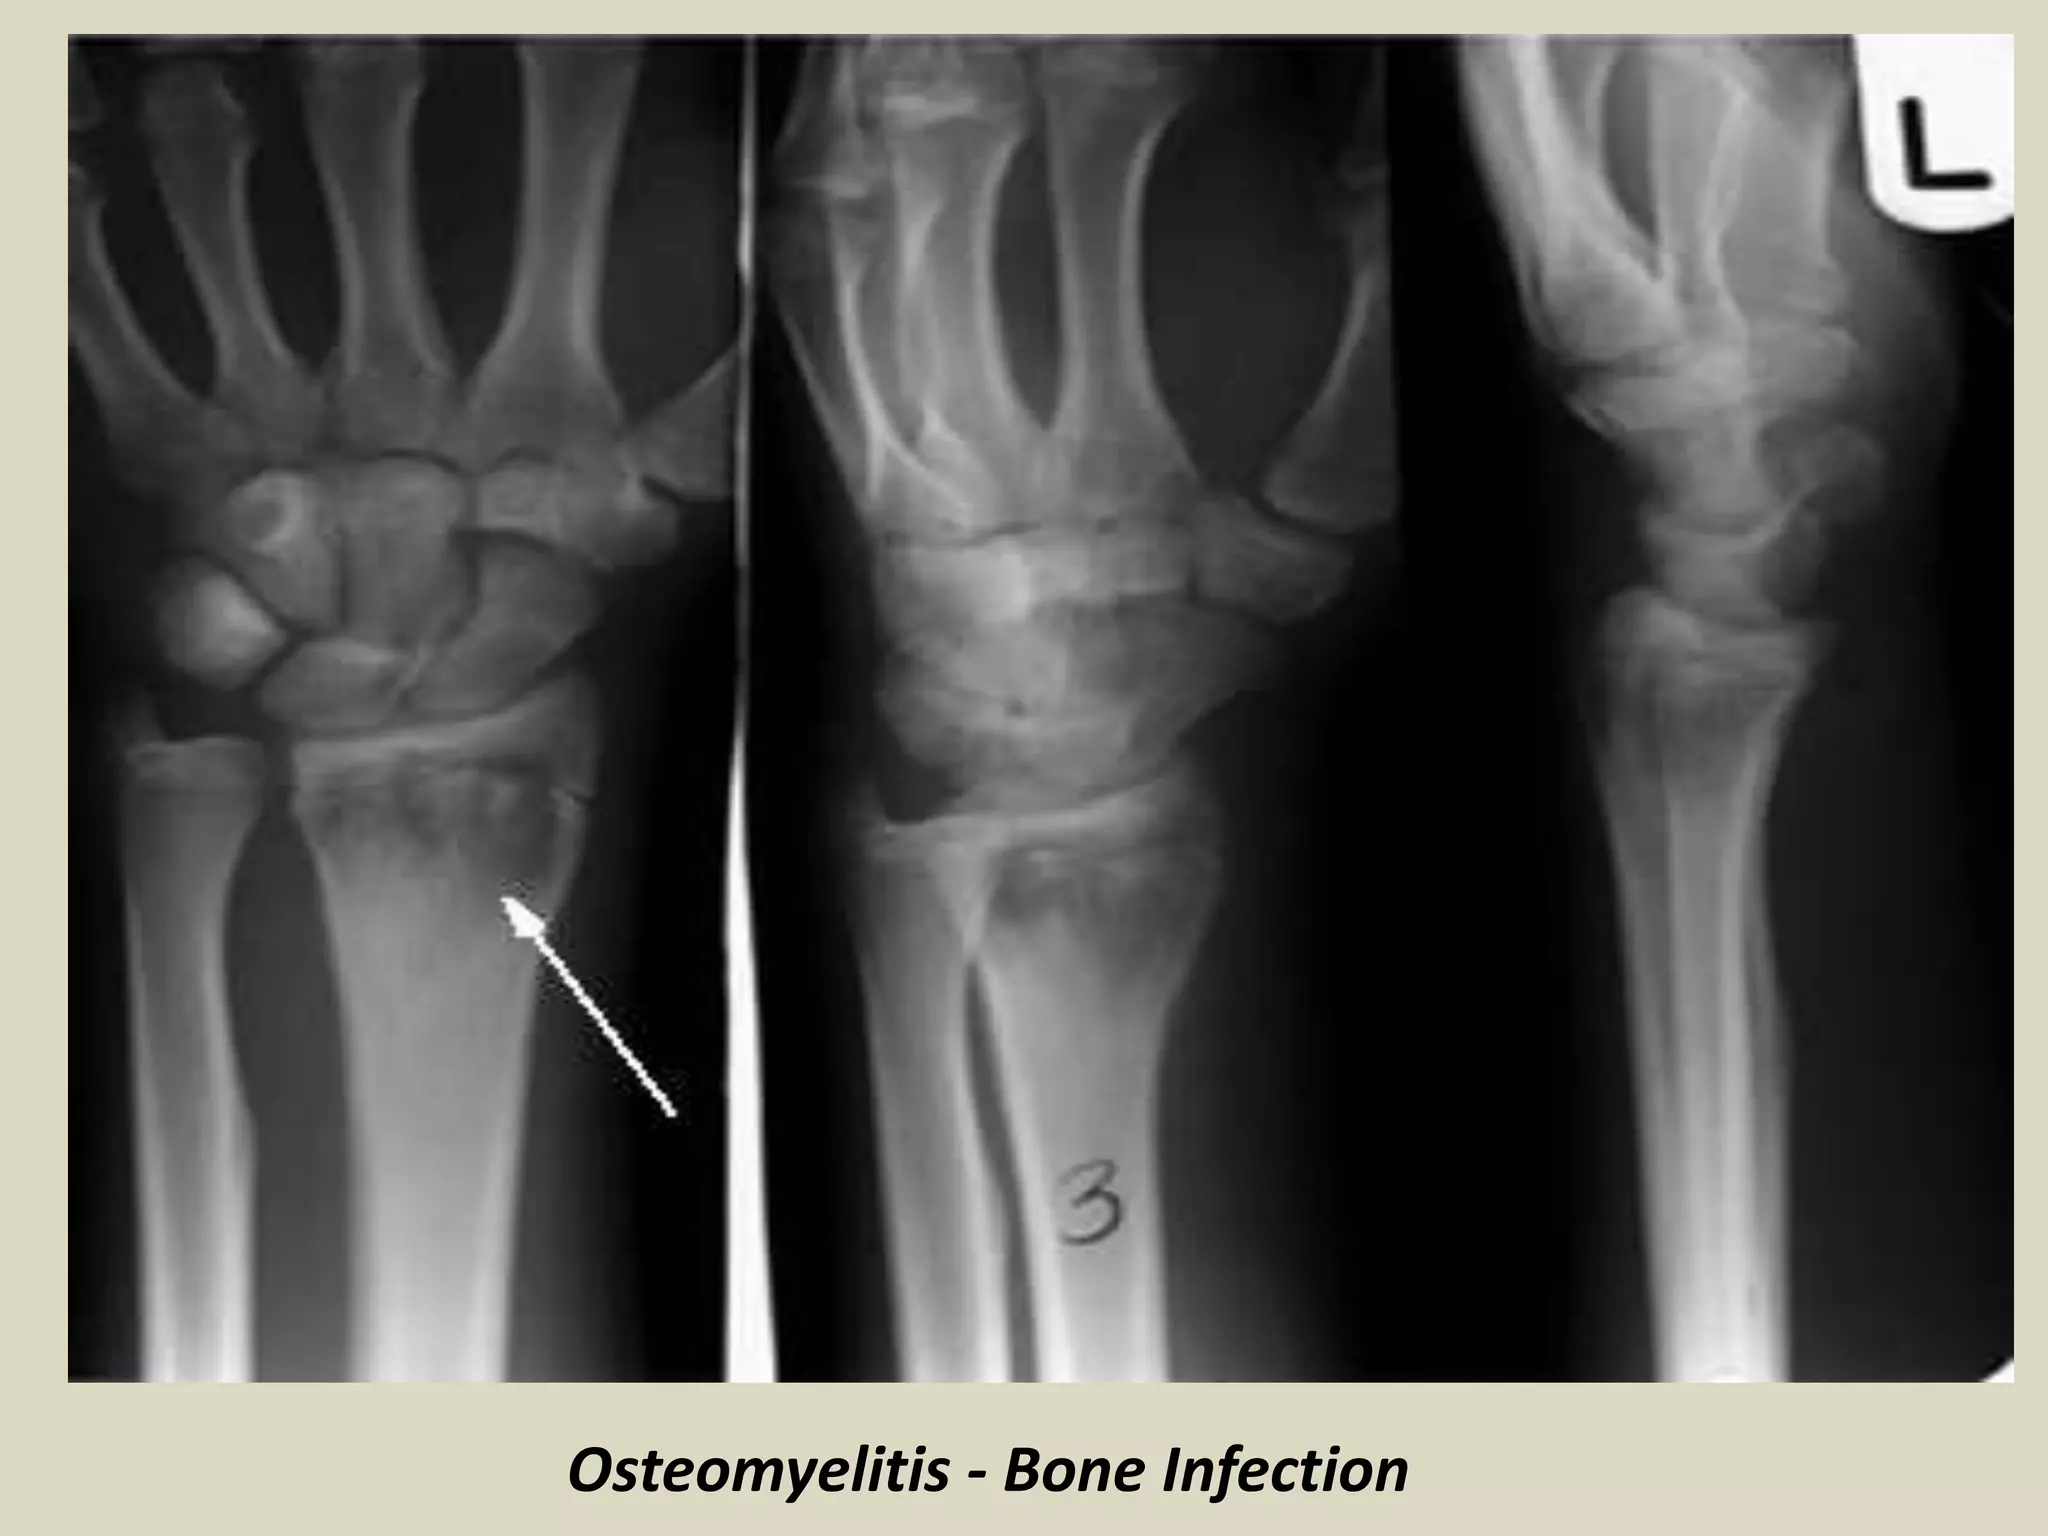

OSTEOMYELITIS

Definition:

Inflammation of bone and marrow also known as infection of bone

May manifest as a primary solitary focus of disease or as a complication of other systemic

disease.

May be caused by different bacterial organisms

Types of osteomyelitis:

Pyogenic Osteomyelitis

Hematogenous osteomyelitis commonly occurs in children.

Staphylococcus aureus is the most common organism responsible for pyogenic osteomyelitis

H. influenzae & group B streptococci are frequent pathogens in neonatal infection.

Gram negative organisms are isolated from patients with genitourinary infection or who are

IV drug abusers

Almost always caused by bacteria.

Organisms reach to the bone by:

1 hematogenous spread

2 extension from a contiguous site

3 direct implantation

The latter (3) occurs as a complication of a compound fracture or of surgery.

Symptoms:

High fever, localized pain and swelling

Labs:

high white cell count, high ESR.

Radiology:

Lytic focus of bone destruction with peripheral zone of sclerosis and reactive

periosteum.

Hot spots on bone scan.

MRI: increased signal intensity in the medullary space.

D.D.: small round blue cell tumor

Chronic osteomyelitis:

One week after the infection, host response evolves with infiltration by chronic

inflammatory cells and release of cytokines which in turn stimulates osteoclastic

bone resorption, ingrowth of fibrous tissue and reactive new bone formation.

Reactive bone in the form of a living tissue around the segment of necrotic bone

(sequestrum) is known as involucrum.

Variants of osteomyelitis:

Brodie abscess – small intraosseous abscess that frequently involves the cortex

and is walled of by reactive bone. It may mimic tumor.

Sclerosing osteomyelitis of Garre affects the jaw bone with extensive new bone

formation.

Chronic Recurrent Multifocal Osteomyelitis.

Osteomyelitis - Bone Infection

Patient with osteomyelitis. The radiograph shows thickening

of the cortical bone and an ovoid central lucency.